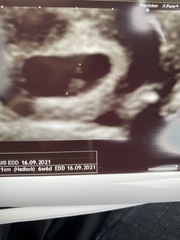

@Moominmiss @Juno231thank you both so much. I saw my baby bean 🥰. First thing I noticed was the super strong heartbeat. Measuring 6wks and 6days so only two days behind what I thought. Bean is 1cm big!! Crazy!

Tracking your cycle and possible BFP using RHR - part 5

@mumof23188 omg they’re amazing photos!!